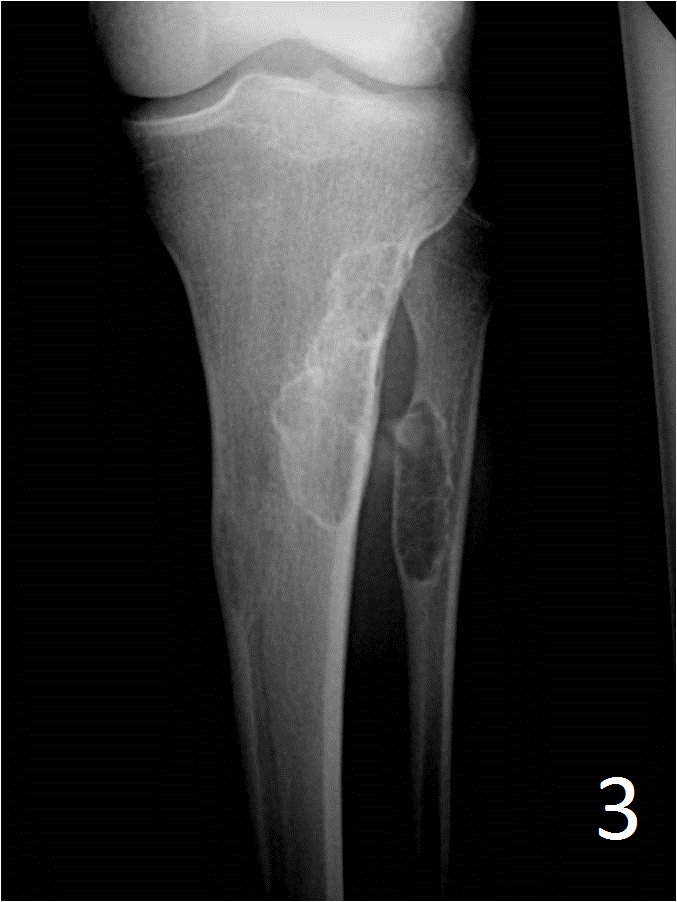

From ar.inspiredpencil.com

Ossifying Fibroma Tibia Radiology Non Ossifying Fibroma The lesions are usually asymptomatic and found incidentally on imaging studies. Nof is a do not touch lesion. Fibroxanthomas can be divided into: Nonossifying fibromas (nofs) are the most common benign (not cancerous) bone tumor in children. Usually a “don't touch” lesion. Fibrous cortical defect (fcd) is a fibroxantoma smaller than 2 cm. It is estimated that 30 to 40%. Radiology Non Ossifying Fibroma.